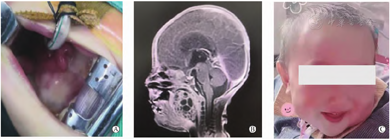

男,胎龄34+3周,孕晚期彩超排畸检查发现口腔内肿物,因胎盘早剥、宫内窘迫,剖宫产,出生体重2. 4 kg。由外院转入,出生后极度呼吸困难,给予气管插管辅助呼吸。查体:口腔内肿物约4. 1 cm× 3. 9 cm,阻塞气道(图3A) ,颈软,三凹征阳性,双肺可闻及干湿性啰音。心腹无特殊,肢体肌张力正常,新生儿原始反射存在。辅助检查: AFP显著增高,遗传代谢病筛查无异常。动脉血气分析、血糖、电解质、肝功能、血常规、凝血常规等在正常范围。MRI平扫+增强:口咽部囊实性占位,横截面39 mm×41 mm,考虑畸胎瘤(图3B)。病情稳定后手术切除,采用全麻下咽部肿瘤切除+任意皮瓣成形+腭咽成形术顺利切除(图3C)。术后病理:未成熟型畸胎瘤Ⅱ级,灶性伴钙化、间质黏液变(图4)。术后复查AFP仍有增高,住院10 d好转出院。2个月随访,MRI平扫加增强提示左侧咽旁间隙实性占位,考虑复发,3个月时再次手术扩大了切除范围,术后病理为未成熟型畸胎瘤Ⅲ级。1岁时随访,体重10 kg,生长发育评估正常,未进行化疗(图3C)。

注: A为术前NPT; B为增强MRI; C为术后1年随访。

注: A为神经外胚层; B为原始神经管; C为胶质细胞源性蛋白(免疫组化,×20)。